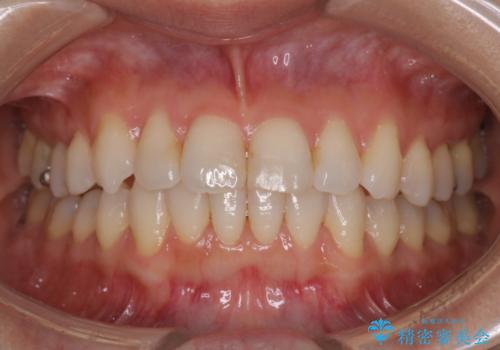

八重歯と前歯のガタガタをインビザラインで

- 八重歯と前歯のガタガタを主訴に来院されました。

目立たず矯正したいとのことでインビザラインで矯正することとしました。

インビザラインで目立たずに治療を終えることができ、喜んでいただけました。